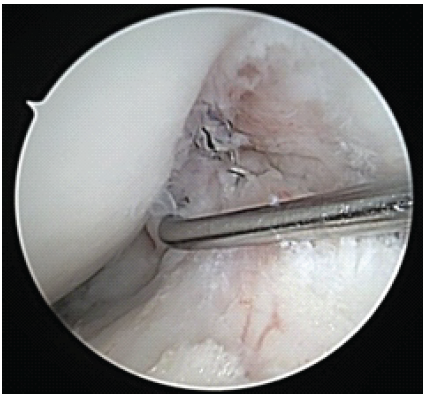

An arthrex fiberloop was placed. With secure fixation on the femoral and tibial stumps, the patient had ACL repair performed in extension and had sutures tied with secure fixation with the aid of a knot pusher. The knot was small and did not impinge in the notch. The patient had a stable ACL to probing and had an excellent endpoint to a gentle Lachman’s at 30° of knee flexion and no impingement along the lateral wall or notch in full extension. Multiple photographs were taken documenting and demonstrating the ACL repair (Figs. 6, 7, 8).

Figure 7: Arthroscopic image of right knee anterior cruciate ligament repair viewed from anterolateral portal at 30° flexion. Stable to probing.